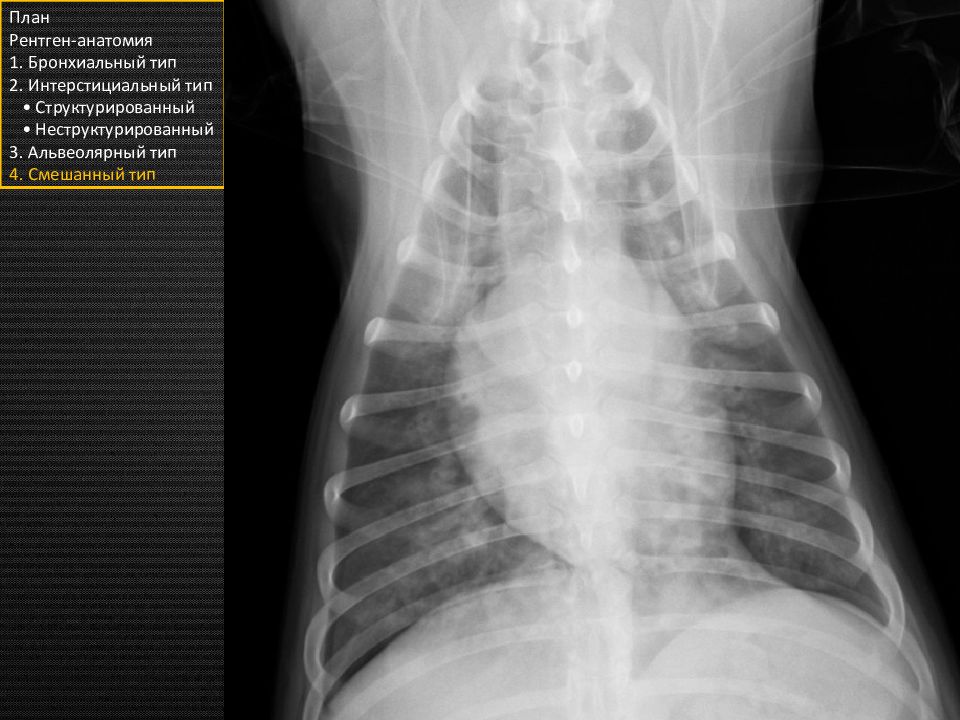

Слайд 8

Прямая проекция План Рентген-анатомия 1. Бронхиальный тип 2. Интерстициальный тип • Структурированный • Неструктурированный 3. Альвеолярный тип 4. Смешанный тип